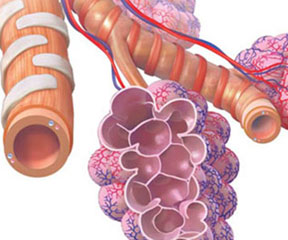

Eric T. Olson Illustration & Design

Eric T. Olson is an accomplished medical illustrator with over a decade of experience creating professional medical illustrations, graphics, and animations for major companies with expertise ranging from patient education to pharmaceutical training. His client list includes such names as Medtronic, Krames Patient Education, Boston Scientific, Novartis, and WebMD.

Eric is well-versed in the use of technology to ensure that the medical imagery he creates is appropriate to fit the needs of the viewer. By combining this technology with fundamental illustration skills, he delivers effective imagery that is equally informative, accurate, and visually appealing.